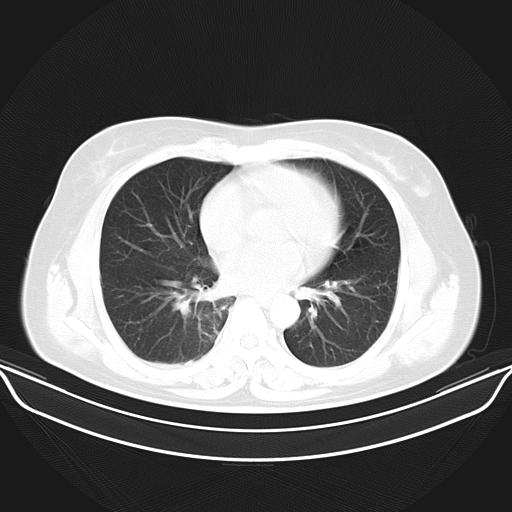

标题: CT22224:肺部肿块

f,48,主因咳嗽咳血来我院检查,无发热。

1)右肺下叶背段团块状软组织密度影;建议抗炎治疗后复查排除肿瘤性病变。2)右侧少量胸腔积液。

谈一谈个人的看法:机器性能应该不错,可惜扫描方法不太正确,即没有及时薄层扫描图像,也没有增强检查,这样的检查方法不正确的图片拿来研究只能是猜一猜:右肺下叶阻塞性改变,建议进一步检查删除肺癌。

支气管镜检查未见异性细胞,抗炎治疗20天,肿块明显缩小。